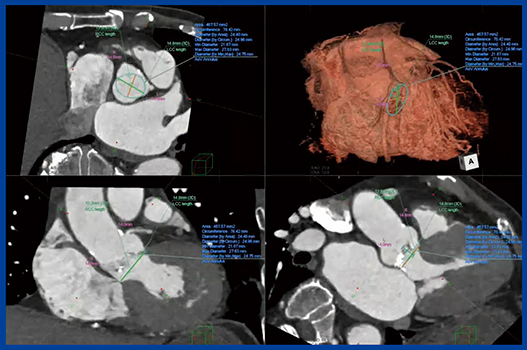

左心耳は,Chickenwing型,Cactus型,Windsock型,Cauliflower型の4つの形態に分類されるが,CTではその形態を俯瞰して観察でき,穿刺位置,シースの進め方などをシミュレーションできる可能性がある。手技の際には,左心耳のくびれの径によってデバイスの大きさを変える必要があるが,CTで左心耳の留置面の最大径を計測することで適切なサイズのデバイス選択に寄与する(図6)。左心耳に対してデバイスサイズが適正でないと留置が困難になることから,形態評価は重要である。

図6 経カテーテル的左心耳閉塞術におけるLAAの計測